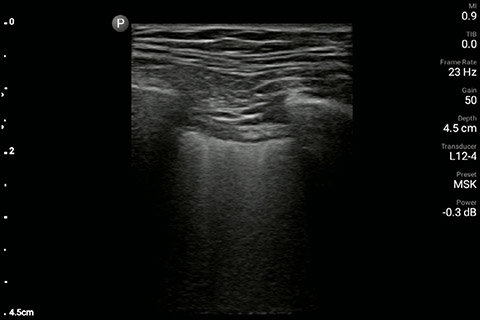

The patient had reduced LV systolic function without new or severe valvular pathology, a dilated, non-collapsing IVC, and diffuse B lines (left greater than right) on lung ultrasound imaging.

M-mode demonstrating lung sliding

Lung image of the right chest